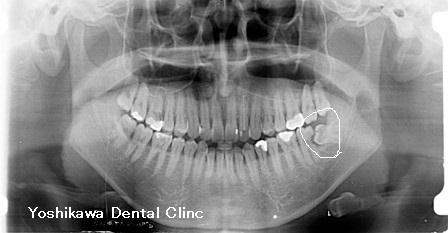

レントゲン診査をすると、水平埋伏歯が手前の歯を圧迫していてその部分が虫歯になっているのが観察されました。そこの虫歯による歯髄炎と診断しました。

レントゲンの○の部分が虫歯・埋伏智歯です。かなり大きな虫歯なのがわかります。